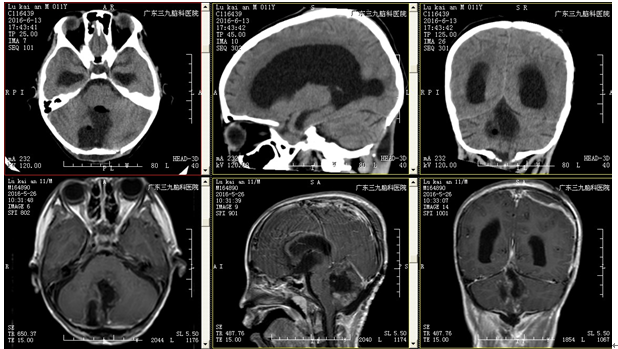

治疗:入院后予完善相关检查,查头颅CTA及MRI示:1.四脑室占位性病变;2.梗阻性脑积水;3.慢性枕骨大孔疝。在全麻下行四脑室肿瘤切除术,术程顺利,术后复查头颅CT、MRI示:呈术后改变,肿瘤全切除,幕上脑室系统扩大较前有所减轻。术后病理结果回报:中枢神经细胞瘤(WHOII级)。出院情况:患者一般情况可,无诉头晕头痛,无呕吐以及肢体抽搐等不适;查体:神志清楚,正确对答以及遵嘱活动,双侧瞳孔等圆等大,对光反射灵敏,颈无抵抗,手术切口I/甲愈合,四肢肌力5级,肌张力正常,生理反射存在,病理征未引出。

治疗后检查